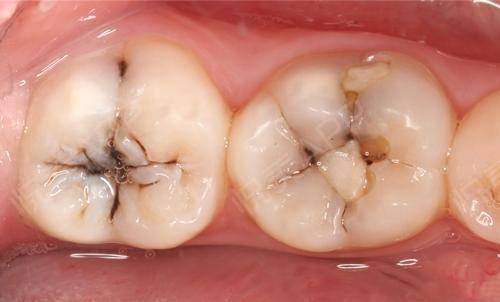

很多小伙伴有过这样的经历:牙疼得翻天覆地、彻夜难眠,心想“一定要找个时间去看牙!”但是一不疼了又想“看牙太可怕了,还是以后再说吧!”结果一拖再拖,反而变本加厉,无奈只能鼓起勇气去看了牙医,上来就想让医生补掉蛀牙,但是这种情况往往已经没办法直接补牙了…… 牙齿龋坏可以分为哪几种? 哪些情况可以直接补牙? 根据蛀牙的深浅,可以分为以下几种: 浅龋 牙齿咬合面有较深的黑线,常见于后牙,说明开始蛀牙了,牙釉质被破坏。这时候往往没有任何不适的症状,容易被忽视。 中龋和深龋 牙齿出现龋洞,冷热酸甜刺激时会敏感,或者食物残渣滞留在龋洞内时会引起酸痛,这种情况说明细菌已经侵入到牙本质中层或深层,如果没有明显的自发性疼痛,大部分情况还是可以进行直接充填的。 而又有哪些牙齿不能直接补牙呢? 有什么治疗的方法呢? 1.蛀牙在无任何刺激的情况下,出现夜间痛或自发痛情况,说明牙神经已经受到细菌感染,发生了牙髓炎,这种情况需要进行根管治疗。 2.蛀牙时间过长,牙神经已经感染坏死,引起牙根发炎。这种情况需要医生结合临床检查和X线片检查,判断牙齿龋坏的大小、根尖炎症的程度,以判断牙齿是否可以保留。若可以保留,即进行根管治疗;若无法保留,则需要拔除。 3.蛀牙面积过大且深,直接补牙极易脱落,效果较差。这种情况需要进行根管治疗后通过修复(全冠、嵌体等)的方法来解决。 小 结 所以,如果大家发现自己有蛀牙,应该尽早修补,以阻止牙齿进一步龋坏。若不及时进行治疗,龋洞就会越来越大,进而引起牙髓炎、根尖炎,甚至残根、残冠,直至需要拔牙。早发现、早治疗,效果就越好,花钱也越少。大家一定要定期检查牙齿哦!